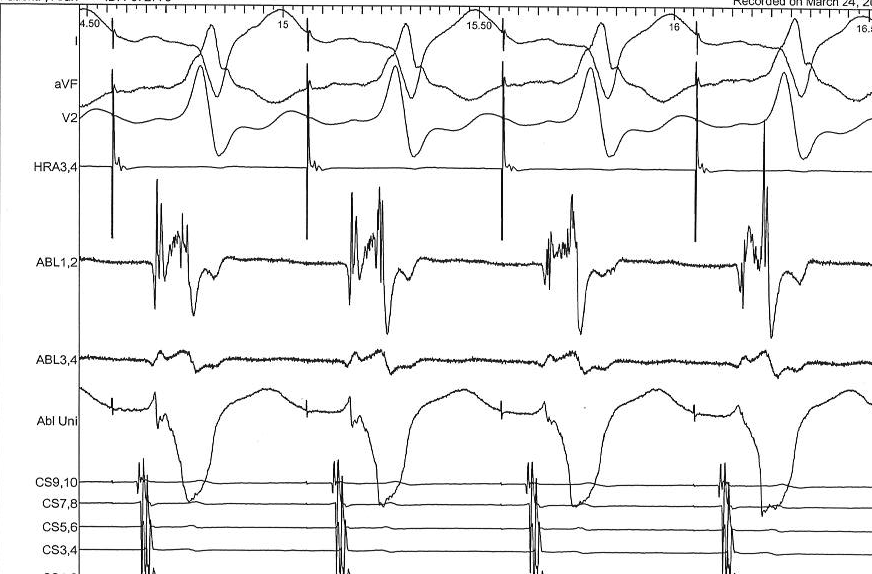

Clipping - When to use

• Avoids signal overlap

• Reduces amplifier saturation obscuring information

• Masks true signal ratios, may hide small potentials

Situations where useful

gain_clipping.jpg

Dont clip ablation signals

abl_clipping1.jpg

abl_clipping2.jpg